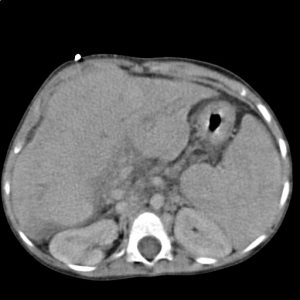

Rakovina plic

Rakovina je strašákem současnosti a můžeme-li věřit předpovědím odborníků, bude ještě hůř. Už nyní umírá na světě v důsledku této nemoci jeden člověk každých pět vteřin, celkem na ni ročně zemře 8 milionů lidí a u 14 milionů je každý rok nově diagnostikována.

U mužů výskyt mírně klesá, u žen roste (podle dat za rok 1977 až 2016 klesl roční výskyt onemocnění u mužů o 9,9 %, u žen vzrostl o 32,8 %).